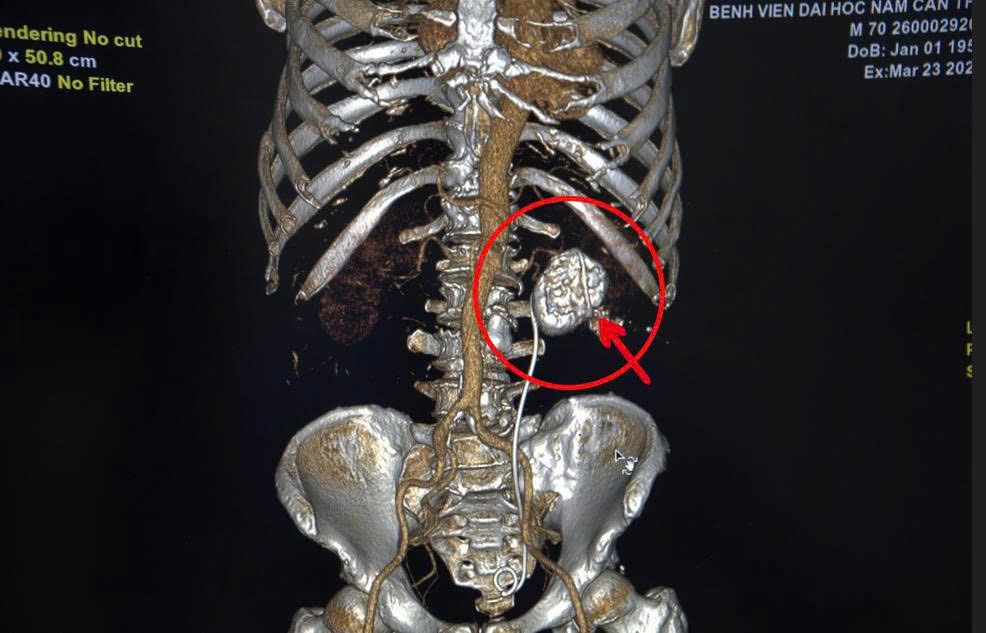

Assoc. Prof. Dr. Dam Van Cuong - Director of the Hospital coordinated with Dr. Pham Quang Thanh and the anesthesia and resuscitation team to perform surgery. The surgery process took place smoothly, taking the entire coral stone with a size of 5.64 cm x 5.80 cm, weighing 83.848 grams.